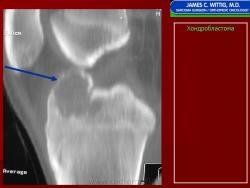

Рентгенологически хондробластома представляет собой сравнительно большой (2-4 см) очаг округлой формы, четко отграниченный от окружающей кости склеротической каймой. На фоне очага в большинстве случаев, но не обязательно определяются плотные включения, напоминающие хлопья ваты.

Рентгенологическая картина. Хондробластома выглядит как небольшой, от 3 до 6 см литический очаг, центрально или эксцентрично расположенный, с четкими контурами, занимающий около половины площади эпифизарной зоны. Хондробластома плоских костей и мелких трубчатых костей больших размеров, может сопровождаться припухлостью мягких тканей, вздутием кости и периостальной реакцией. Распространение процесса на метафизарную зону встречается часто.

Хондробластома — это редкая доброкачественная опухоль, локализующаяся, главным образом, в диафизах и отличающаяся своеобразным клеточным составом. Ткань новообразования представлена овальными, округлыми и веретеновидными клетками, напоминающими незрелые хондроциты (хондробласты). Зрелый гиалиновый хрящ определяется лишь в некоторых опухолях. Возраст больных варьирует от 3 до 72 лет. Мужчины поражаются в два раза чаше женщин. Пациенты предъявляют жалобы на боли в течение нескольких месяцев или лет, у некоторых больных определяются внутрисуставной выпот, припухлость и ограничение движений. Наиболее типичная локализация опухоли — проксимальные эпифизы плечевой и большеберцовой костей, а также дистальный эпифиз бедренной кости. У 20 % больных опухоль развивается в плоских или коротких трубчатых костях, преимущественно в пяточной и таранной. Изредка поражаются кости лицевого черепа, в том числе височная. При рентгенологическом исследовании видна типичная картина злокачественной опухоли остеолитического типа. В большинстве случаев новообразование выходит за пределы эпифиза и распространяется на метафиз. На фоне остеолиза обнаруживаются рассеянные участки обызвествления в виде пунктирных линий, а также разреженный трабекулярный рисунок. Хондробластома, как правило, не выходит за пределы кости, но изредка проникает в полость сустава. В процессе роста опухоли иногда возникает вторичная аневризматическая костная киста. Хондробластома — это доброкачественная опухоль, поэтому для ее лечения используется кюретаж с последующей костной пластикой. У некоторых больных в течение 3 лет после этого возникает рецидив, для лечения которого также используется кюретаж или же резекция опухоли. Примерно 1 % хондробластом отличается агрессивным местным ростом и метастазирует в легкие, причем метастазы могут выявляться спустя многие годы после обнаружения первичного узла. Некоторые хондробластомы прорастают в окружающие мягкие ткани, но при этом не метастазируют. Описаны случаи малигнизации этого новообразования после лучевой терапии с формированием фибро-или остеосаркомы. Макроскопический вид хондробластомы варьирует. Обычно опухоль состоит из зернистой ткани желтовато-серого или буровато-серого цвета, в которой определяются кровоизлияния и аневризматические кисты. Видны также голубовато-серые участки, соответствующие хондроидному матриксу. Точечные желтоватые вкрапления соответствуют очагам обызвествления или реактивного остеогенеза. По периферии опухоли определяется поясок склерозированной костной ткани. Микроскопическая картина зависит, главным образом, от количества хондроидного матрикса, продуцируемого опухолевыми клетками, а также от распространенности некроза, наличия аневризматических кист. Обращает на себя внимание клеточный полиморфизм. Наибольшее число клеток составляют хонлробласты с четкими контурами, в которых определяются округлые или овальные ядра, окруженные зоной просветления. Ядра клеток расщепленные, с глубокими инвагинациями и вдавлениями. Ядерный хроматин выглядит мелкораспыленным или в виде скоплений неправильной формы. Число фигур митоза в опухоли обычно невелико, и они определяются только в 75 % случаев. Лишь изредка это число превышает 4 на 10 полей зрения при большом увеличении микроскопа. Атипичный митоз не встречается. Клеточный атипизм обнаруживается лишь у 20—30 % хондробластом. Обычно это крупные неправильной формы клетки с гиперхромными ядрами. По-видимому, их наличие не является неблагоприятным прогностическим признаком. В некоторых участках границы между хондробластами неотчетливые, и общая картина приобретает вид синцития. Наряду с округлыми элементами в опухоли встречаются и веретеновидные клетки, которые образуют гнездные скопления или же равномерно вкраплены между типичными клетками. Встречаются также многоядерные клетки, часть которых очень похожи на крупные остеокласты. Все вышеописанные клетки дают положительную реакцию на SlOO-протеин, нейронспецифическую энолазу и виментин.